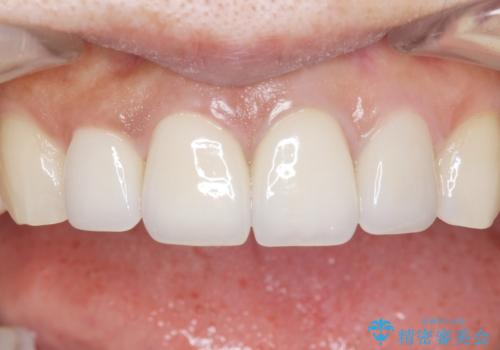

5年前のクラウン装着時と比較したところ、歯肉が成熟し歯間乳頭ができており、より天然歯のように自然に見えました。

患者様の良好なセルフケアと精密な適合の良いクラウンにより、歯肉の腫脹や退縮も認められませんでした。

5年前に行った治療に大変ご満足頂き、他の部位も治療やホワイトニングを希望して下さいました。

人工のダイヤモンドにも用いられるジルコニアは、セラミック系素材の中でも圧倒的に丈夫かつ審美的で、劣化しにくく口腔内でも長期間安定した状態を保つことができます。

クラウンの種類:ジルコニアオールセラミッククラウン スタンダード